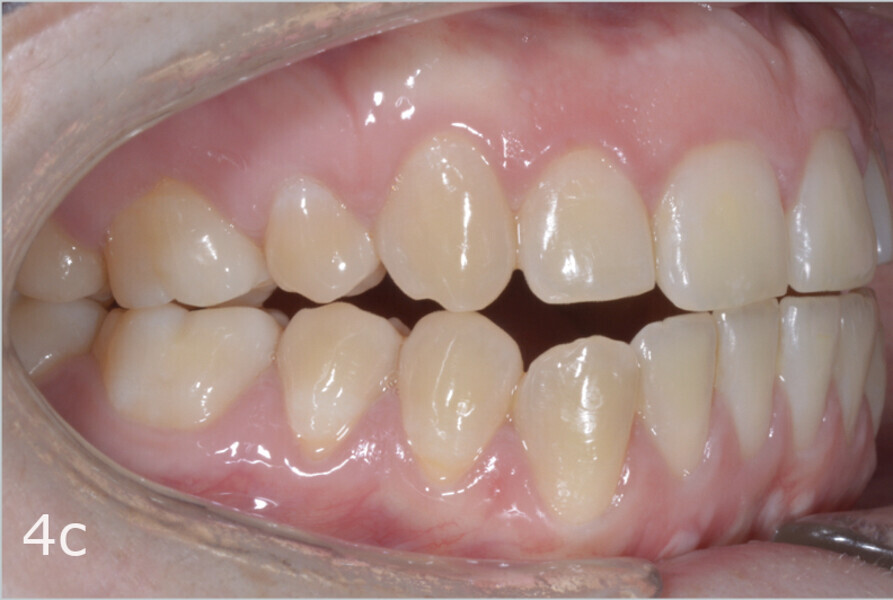

The 23-year-old dolichofacial female patient complained of not being able to chew properly. Facial examination showed a convex profile, an enlarged lower facial height, and a skeletal Class III malocclusion (Figs. 1–3). Intra-oral examination revealed an Angle Class III right subdivision malocclusion, anterior open bite, no overjet and a maxillary dental midline deviated about 3 mm to the right compared with the mandibular dental midline (Fig. 4). The panoramic radiograph confirmed previous extraction of the maxillary right first premolar and the presence of all four third molars (Figs. 5 & 6).

The treatment objectives included closing the anterior open bite, achieving a bilateral Angle Class I relationship and a proper overjet and overbite, correcting the midline discrepancies, and achieving a profile harmonisation. The treatment plan consisted of orthodontic camouflage treatment with asymmetric distalisation in three of the four quadrants using Invisalign aligners (Align Technology) and third molar extraction. The Invisalign Comprehensive package was chosen, and 63 pairs of aligners were used (Figs. 7–10). Each aligner was worn for 20 hours a day for one week each. The use of Class III elastics on both sides was indicated. Afterwards, ten refinement aligners were needed to improve the interdigitation on the right side (Figs. 11 & 12).